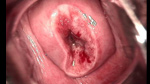

婦科leep錐切手術 CIN2-3

• CIN 2-3CIN 2-3